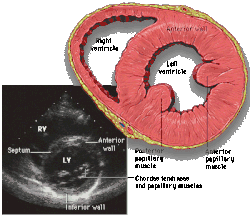

![]() Parasternal short axis |

| Each figure contains a TTE with a black background, and a corresponding colored illustration. | Patrick J. Lynch and C. Carl Jaffe, Yale University, 2006. | ||||||||||

| Click on a figure to enlarge it and see some parts of the heart identified. RV, right ventricle; LV, left ventricle; RA, right atrium; LA, left atrium; TV, tricuspid valve; MV, mitral valve; AV, aortic valve; RVOT, right ventricular outflow tract; LVOT, left ventricular outflow tract | |||||||||||